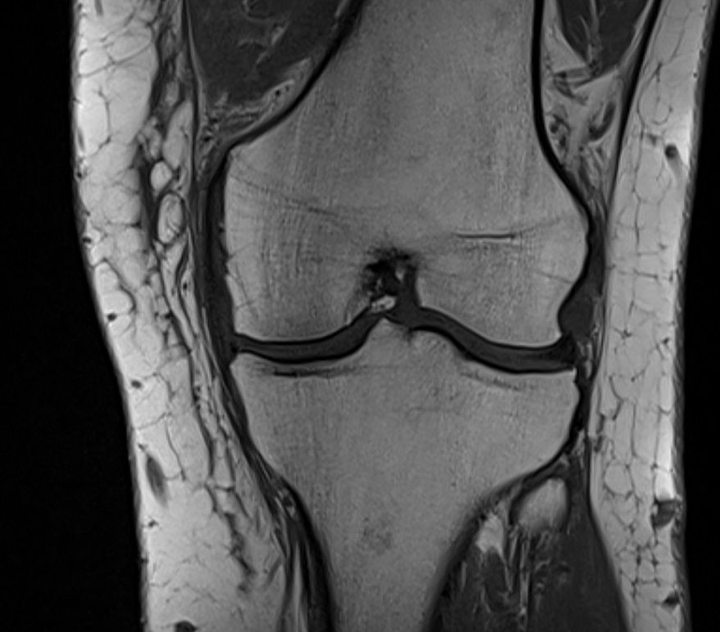

MRT Aufnahme eines Kniegelenks